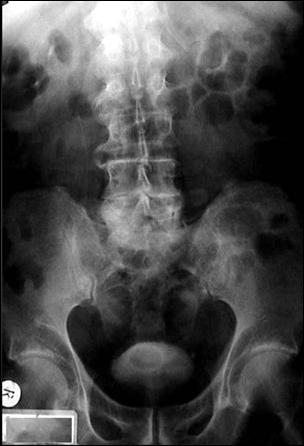

1. Diagnosticul diferential cu litiaza vezicala radiotransparenta

Ecografia vezicii urinare evidentiaza imagine hiperecogena, cu con de umbra posterioara (calcul)

Figura 54. Imagine radiotransparenta (2,5/1,8 cm, vizibila pe cistografie) |